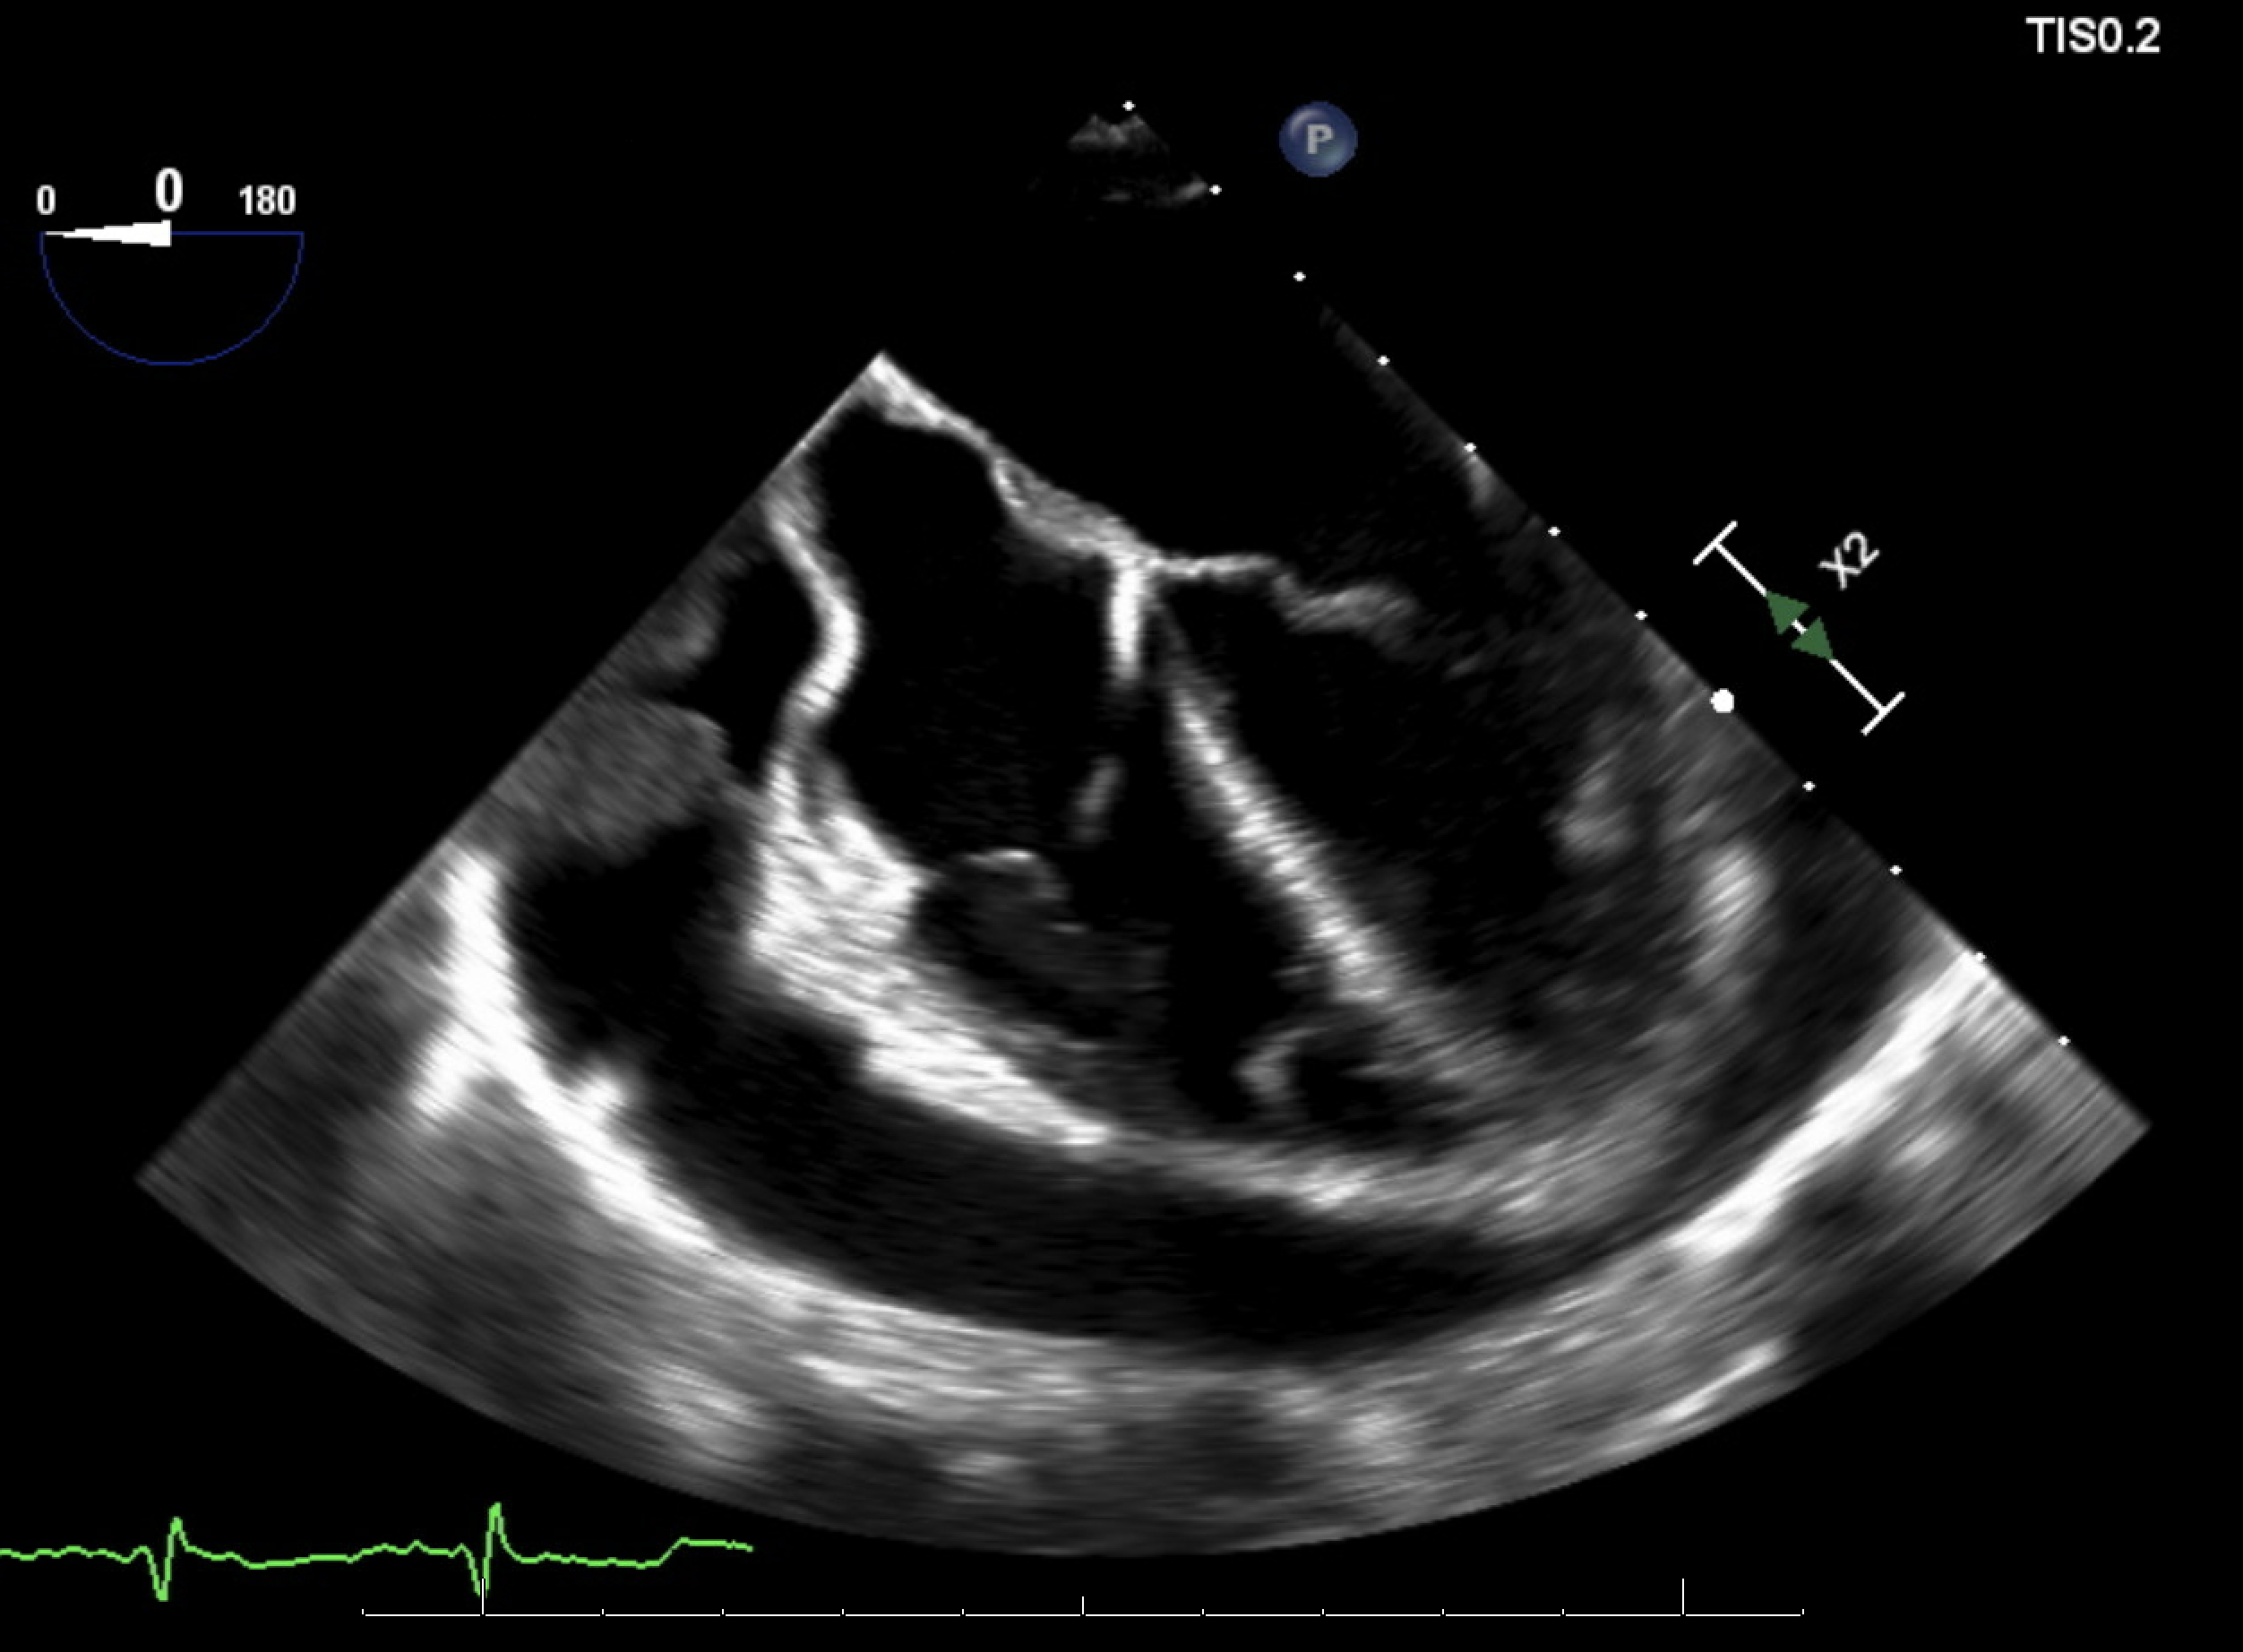

Due to persistent bacteremia and worsening hemodynamics, a repeat TEE was performed, which revealed a new, large circumferential pericardial effusion with right atrial systolic collapse, right ventricular diastolic collapse, plethoric IVC, a 1.4 × 0.8 cm highly mobile vegetation on the mitral valve subvalvular apparatus, and multiple large echogenic structures in the pericardial space concerning for vegetation. Pericardiocentesis revealed a purulent, MRSA-positive fluid, confirming purulent pericarditis. The antibiotics regimen was intensified and the patient was transferred to a higher level of care facility for cardiac surgery evaluation.